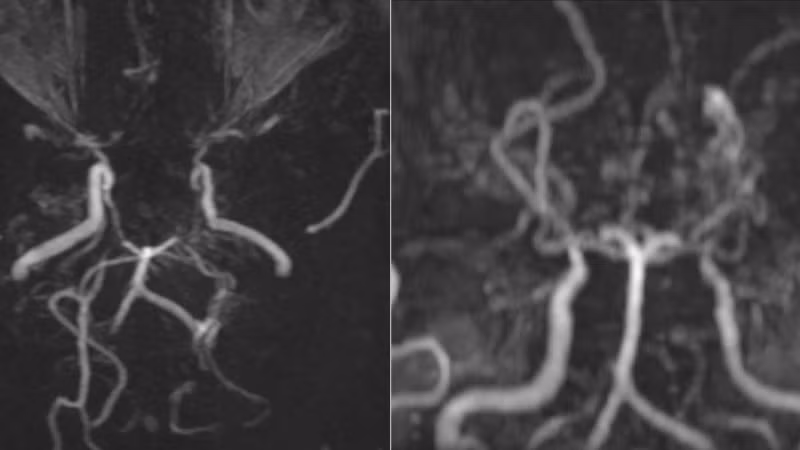

Các mạch máu não của bệnh nhân nhìn như “làn khói thuốc lá” trên phim chụp MRI

Kết quả MRI cho thấy, hình ảnh tổn thương hẹp tắc động mạch cảnh trong hai bên và các nhánh của đa giác Willis, xung quanh hình thành tuần hoàn bàng hệ với nhiều mạch máu nhỏ bất thường. Trên phim chụp mạch não, các mạch này tạo thành đám, tỏa mờ như “làn khói thuốc lá” – dấu hiệu đặc trưng của bệnh Moyamoya.

Đồng thời, trên chuỗi xung FLAIR, xuất hiện những dải tín hiệu sáng chạy dọc theo rãnh cuộn não, gợi hình ảnh “dây thường xuân” len lỏi trên bề mặt, phản ánh sự gia tăng tuần hoàn bàng hệ màng mềm để bù đắp cho tình trạng thiếu máu não do tắc nhánh mạch não.